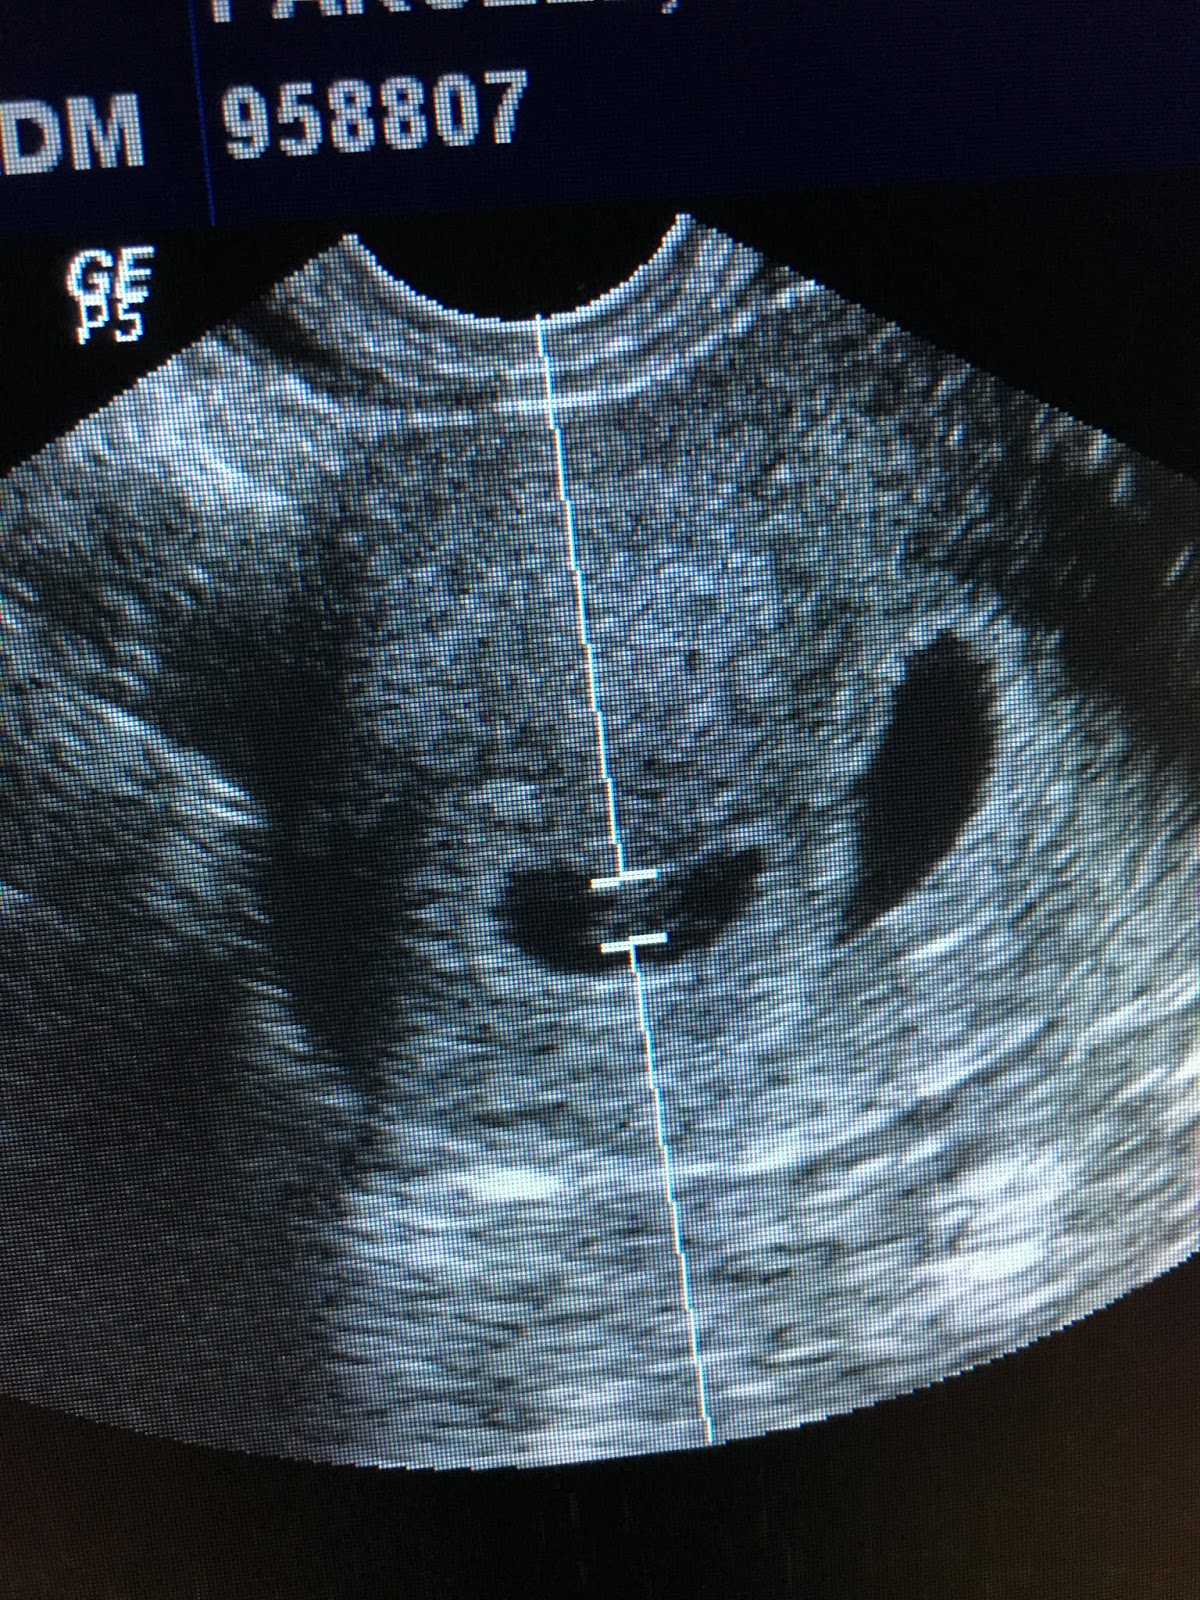

We were about 10 minutes early to our appointment so we signed in and sat in the waiting room. When we were called back, the nurse asked me if I needed to “empty my bladder” and I said no, then wondered if I should have said yes because I forgot if it was best to have an empty or full bladder for an ultrasound. I undressed from the waist down and Ashley (my ultrasound tech and friend), popped her head in the room and said, “I can’t wait any longer!” joking with us. She used an intravaginal ultrasound as they always do there, and she saw that my bladder was full. I asked her if she wanted me to go use the restroom but she said she couldn’t wait any longer to find out. Your dad walked down by her and she started to smile really big. Your dad’s head was blocking the screen but I could see it a little bit and I thought I saw twins. I had googled what twins look like in the uterus (of course ;)) but he hadn’t and she was looking at him expecting him to see it. She said, “I’m just looking at the twins” and I screamed so loud!! Another nurse came in and said, “Is it twins? I called it!”

We then got to listen to the heartbeats of our sweet little babies. It was totally amazing and surreal! I keep telling your dad that I can’t believe I have 3 heartbeats in my body right now. Ashley had a hard time getting the heartbeats because I was so excited and was moving around I guess. I dare anyone who has just found out they are having twins after trying for so many years, 3 IUI’s, 3 rounds of IVF and hundreds of shots to hold still. Joy filled my whole body!

Comparing the little embryos, to the embryos in my uterus the day of transfer (the two white specks in the middle), to the two little babies making themselves at home!

Look at the sweet little peanuts!